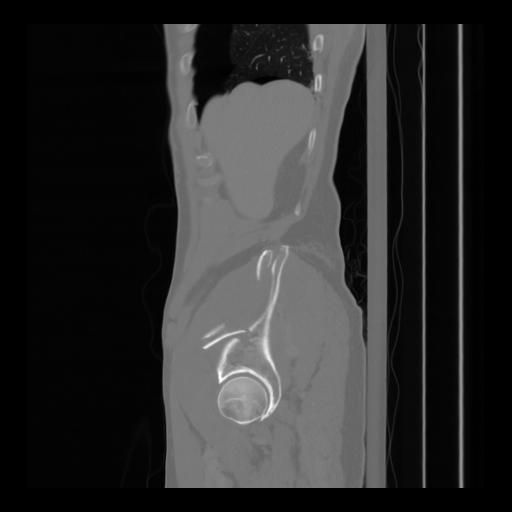

36 CUERPO,CE,Sagittal,3.000,CUERPO,Sagittal,